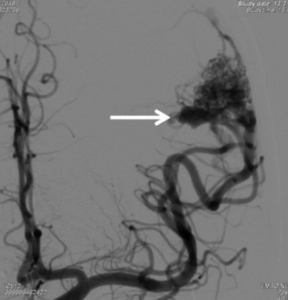

一名37岁女士被发现在家中晕倒、丧失意识,被送入公立医院。病人和家属获告知CT电脑扫描、脑电波图和所有血液化验结果一切正常,医生仍然没有临床线索来确定她晕厥的原因。于是病人出院后咨询脑血管外科医生意见,医生审查公立医院的血液检查报告时发现病人血清肌酶素曾经非常高,表示她晕倒、意识不清的原因是严重强直阵挛性脑癫痫症发作。医生于是为她进行3D三维立体磁力共振脑血管造影,造影显示病人左前额大脑脑叶藏有一个3cm的先天性动静脉畸形血管瘤,并有少量最近出血的现象,是她失去意识和脑痫症的原因。动态 3D 三维立体数码递减脑血管造影(Dynamic 3D Digital Subtraction Cerebral Angiogram DSA) 确定血管瘤内血液的流动模式。在4 小时的显微镜下,血管外科医生在血管瘤旁边的脑部看到血铁黄素的旧有残留血液,血管瘤和瘀血均被彻底移除。病人脑部神经功能得以完好保全,手术后两天出院,10年来癫痫症再没有发作。

![]() | ![]() |

3D 三维立体脑血管造影显示,左边大脑有先天性的脑血管动静脉畸形 (AVM)。